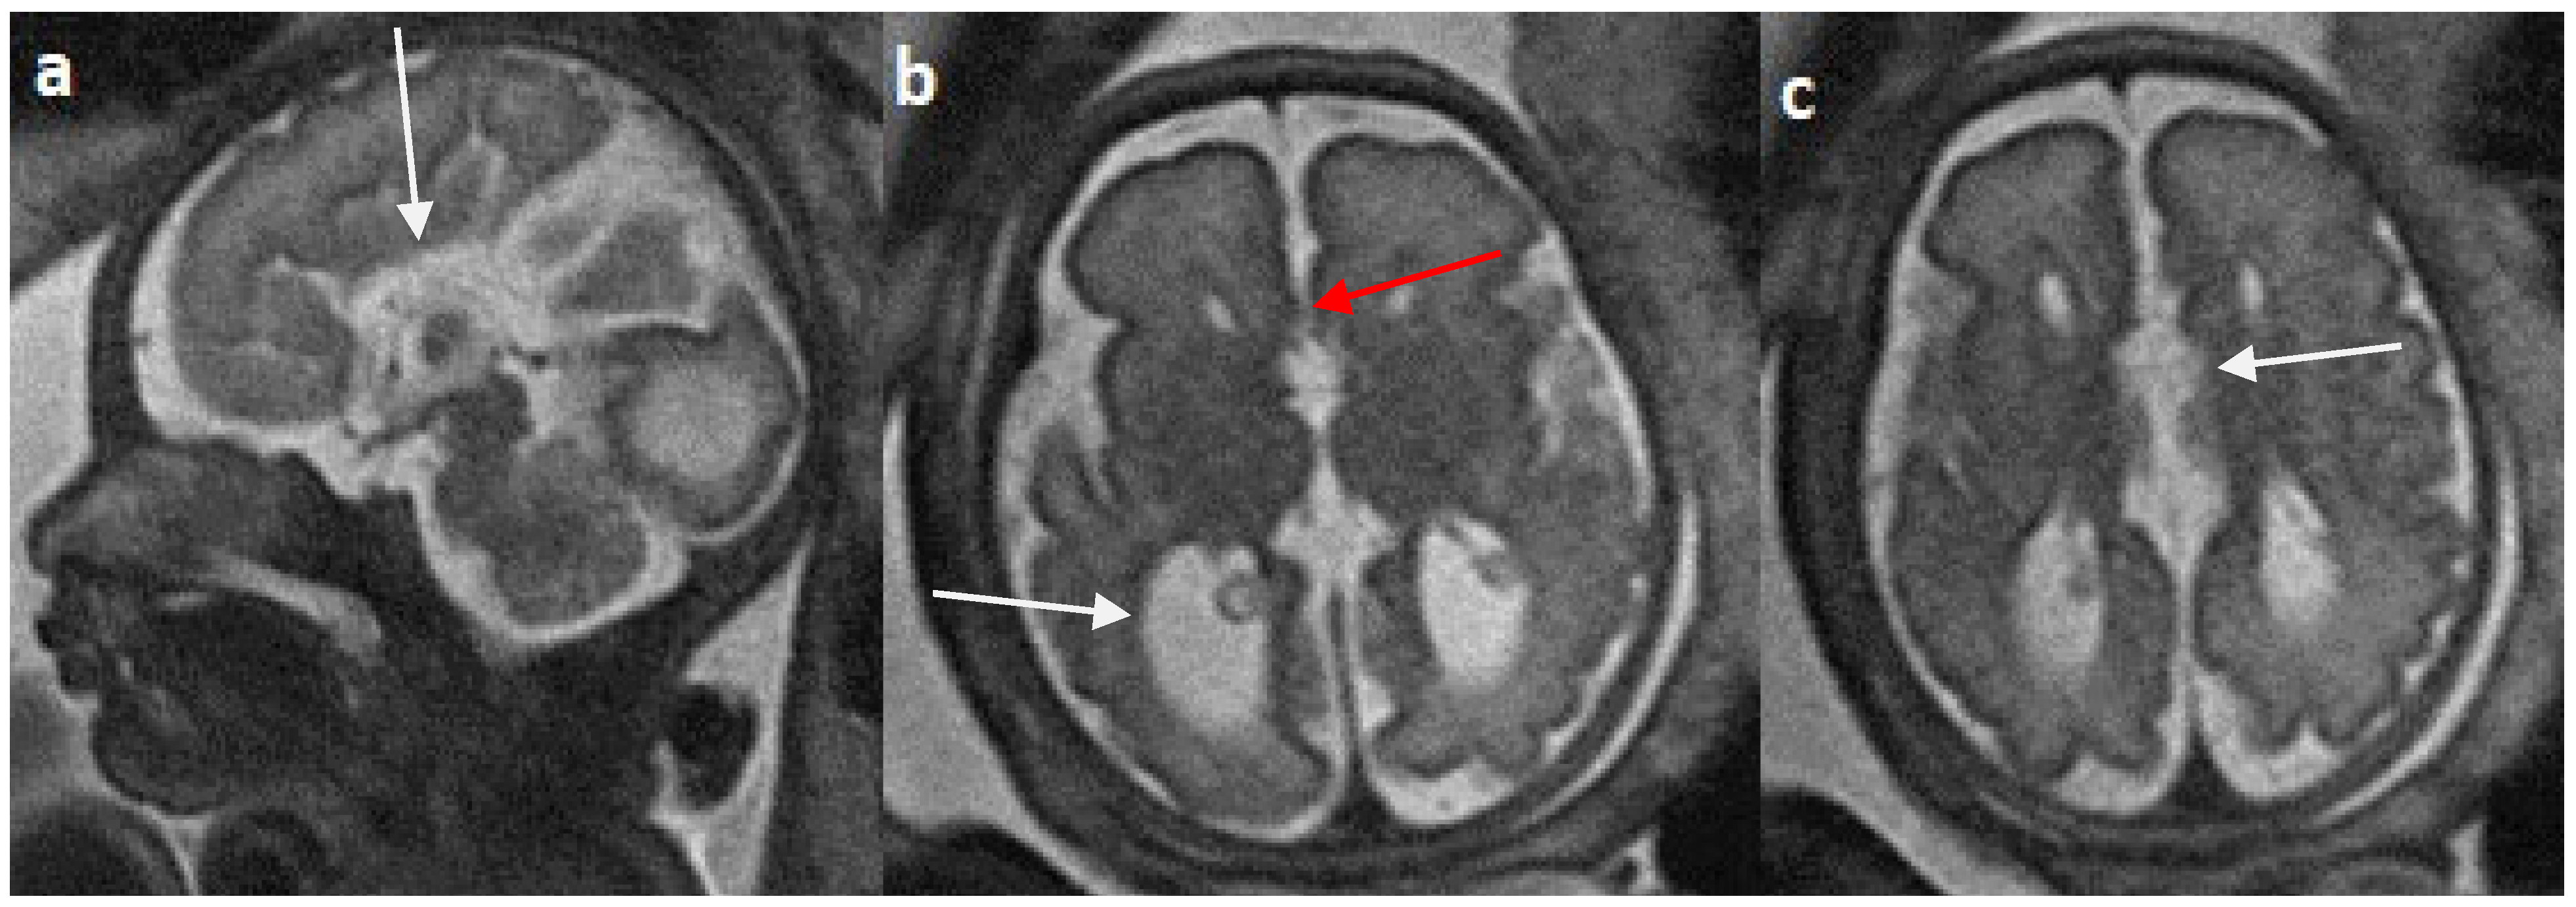

Colpocephaly is seen in 13/24 cases (54%) (Figure 5). Of them, 12 cases had complete agenesis, and one case had hypoplasia. Absent septum pellucidum is seen in 5/24 cases (20.8%) (Figure 6); 4 cases had complete agenesis, and one case had hypoplasia. Probst bundles are identified only in the isolated form of CCA and account for 3/19 cases (15.7%) of complete agenesis and 3/4 cases of the isolated form of CCA (Figure 7). Probst bundles are not seen in other subclasses of CCA. Ventriculomegaly is seen in 7/24 cases with an incidence rate of 0.29%, 5 cases had complete agenesis, and 1 case each had hypoplasia and hypoplasia with dysplasia.

Figure 5.

Fetal MRI images of a 31 gestational weeks aged fetus with complete agenesis of the corpus callosum. (a) A T2-weighted sequence image in sagittal plane shows that the corpus callosum is not visible (white arrow). (b) A T2-weighted sequence image in axial plane shows a “teardrop”-like dilation in the posterior horn of bilateral lateral ventricles suggestive of colpocephaly (white arrow) and absence of corpus callosum and septum pellucidum (red arrow) in the midline. (c) A T2-weighted axial image shows a small interhemispheric fluid collection/cyst in the midline. (arrow). No Probst bundles are observed.